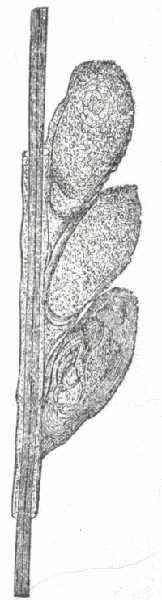

Fig. 7.

A normal sebaceous gland in connection with a lanugo hair. (After Neumann.)

a, Capsule; b, fatty secretion; c, h, secreting cells; d, root of lanugo hair; e, hair-sac; f, hair-shaft; g, acini of sebaceous gland.